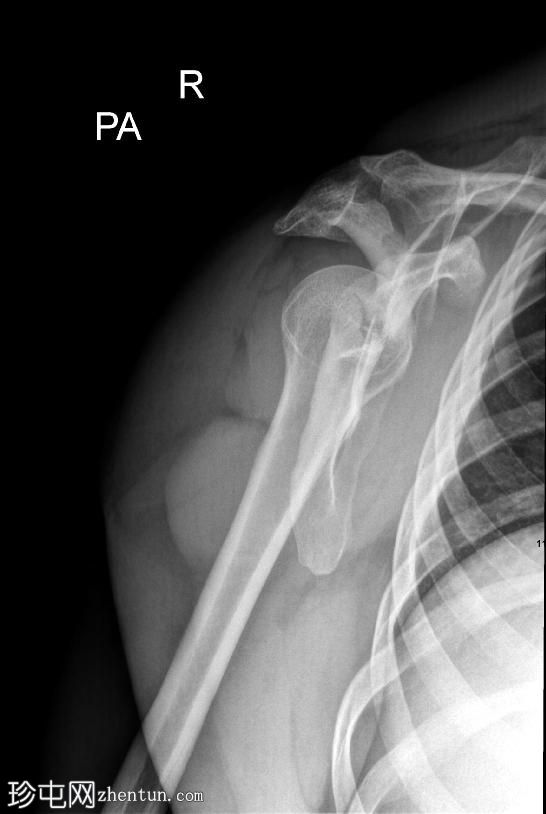

1.jpeg

正面

右侧肩胛骨骨折,累及肩胛盂、肩胛颈和肩胛体。肱骨头与肩胛窝对位良好,提示无肩关节脱位。

肩部和肩胛骨周围有弥漫性软组织肿胀。

本例X光片显示骨折累及肩胛盂、肩胛颈和肩胛体,提示力量显著通过肩胛带传递。肩胛盂受累尤为重要,因为它可能损害盂肱关节的稳定性和关节的一致性。

肩关节无脱位且肱骨头排列完整是有利的发现。然而,由于解剖结构复杂且可能在关节内延伸,建议进行CT扫描以更好地明确骨折形态并指导手术计划。